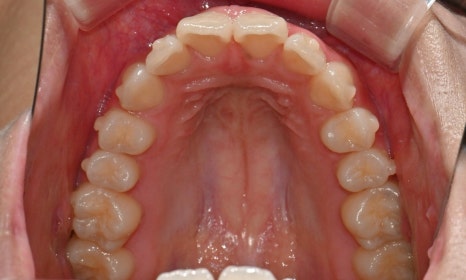

2025.3. 초진 (앞니 경미한 총생과 과개교합) - 연세정원치과

정밀진단 결과 위아래 앞니가 약간 겹쳐 있어 배열이 고르지 않은 상태였으며, 약간의 과개교합이 동반된 상태였습니다. 다만 골격적인 문제나 안모 불균형은 없었고, 측면에서도 돌출감 없이 비교적 안정적인 안모를 유지하고 있었습니다.

이러한 점을 종합적으로 고려해보았을 때 치아 배열의 개선과 교합 조정을 중심으로 한 비발치 교정 치료가 적합한 케이스였습니다. 또한 환자가 고등학생이라는 점, 그리고 학업과 일상 생활에 대한 부담을 최소화하고 싶다는 보호자의 의견을 반영하여, 인비절라인으로 선택하게 되었습니다.

이번 케이스는 인비절라인 Comprehensive로 치료를 진행하였으며, 치아 이동은 과도하지 않게 단계적으로 진행하기 위해 치간삭제를 최소한으로 적용하며 공간을 확보하는 방향으로, 총 33단계의 장치를 통해 치아 이동을 계획하였습니다.